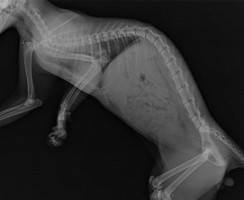

Когда над питомцем нависла опасность: внутреннее кровотечение у кошек

Каждый владелец кошки знает, что крохотный мяукающий комочек, принесённый в дом, очень быстро становится полноправным членом семьи. Питомцы дарят нам свою бескорыстную любовь и ...